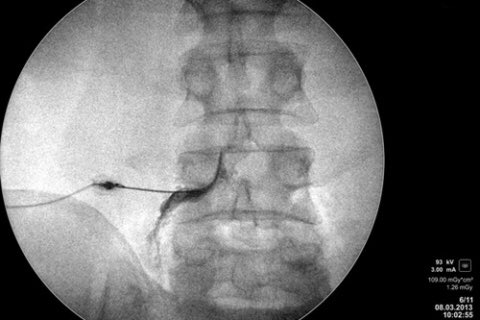

هناك بعض الإجراءات التي تتبع خلال حقن الإبرة وهي :

تحقن عن طريق أشعة أكس ( لتحديد المكان الصحيح للإبرة ) … يتبع